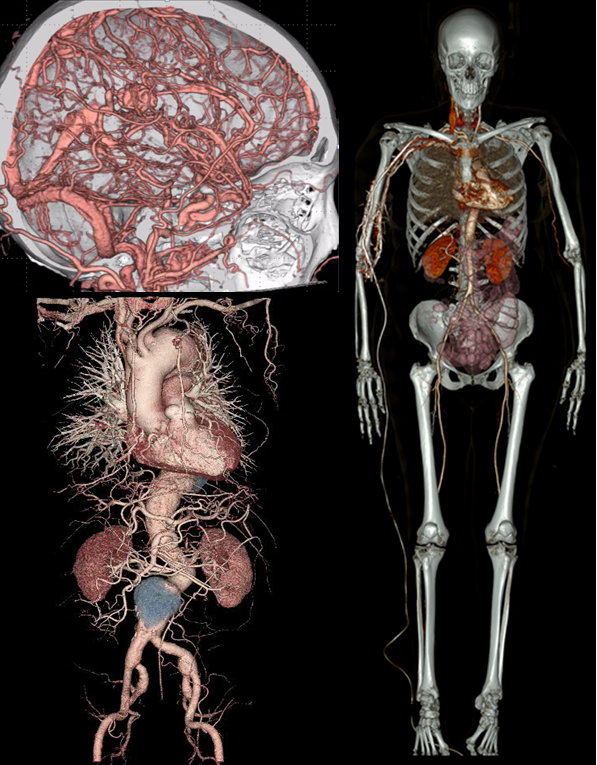

造影CT

造影剤という薬を注射して撮影を行います。撮影する部位や方法の違いで、何回か撮影することがあります。痛みの原因を調べたり、腫瘍が良性か悪性かの精査、血管の狭窄や動脈瘤を見つけることができます。造影剤が入ると血管や腫瘍などがはっきりと写るようになります。 手術前の評価にも使用します。

腹部大動脈瘤手術前

腹部大動脈瘤手術後